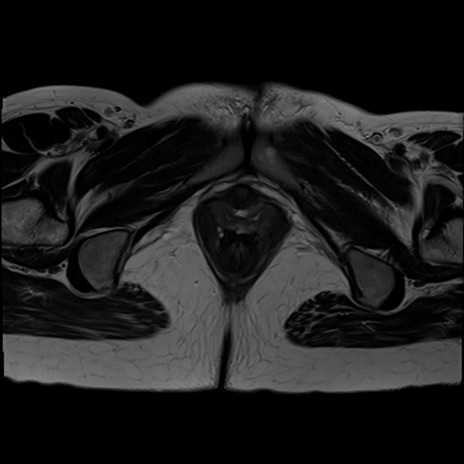

症例39 T2WI(横断像)

MRI(4日後)